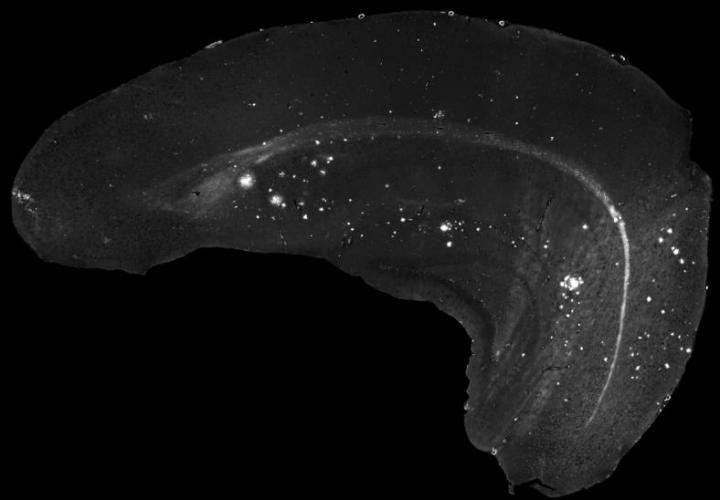

In the current project, which was financed by the German Federal Office for Radiation Protection (BfS), the researchers have been able to demonstrate for the first time in a long-term study in relevant animal models that controlled exposure to low-frequency magnetic fields over a period of up to 18 months does not influence the onset and progression of Alzheimer's disease and ALS. A detailed analysis of the characteristic features of each disease showed that their development was in no way related to exposure to low-frequency magnetic fields. In the case of Alzheimer's disease, this also applied to the formation of pathological amyloid-beta protein plaque in the brain while in the case of ALS, there was no effect on the levels of proteins damaged by oxidative stress in the spinal cord. The inflammatory response in the nervous system that occurs in the course of both diseases was also unaffected during exposure. Moreover, neither learning behavior as an indicator of the progression of Alzheimer's disease nor the onset and the duration of ALS were influenced by the magnetic fields. "These results show that exposure to low-frequency magnetic fields has no effect on either disease-related molecular processes or on potential, as yet unknown, disease mechanisms," said Clement. "Our findings thus tend to confirm the results of previous epidemiological studies that indicate no damaging effects of low-frequency magnetic fields."